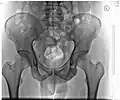

Becken -

Röntgenbild eines Beckens (Mann, 46 Jahre) -